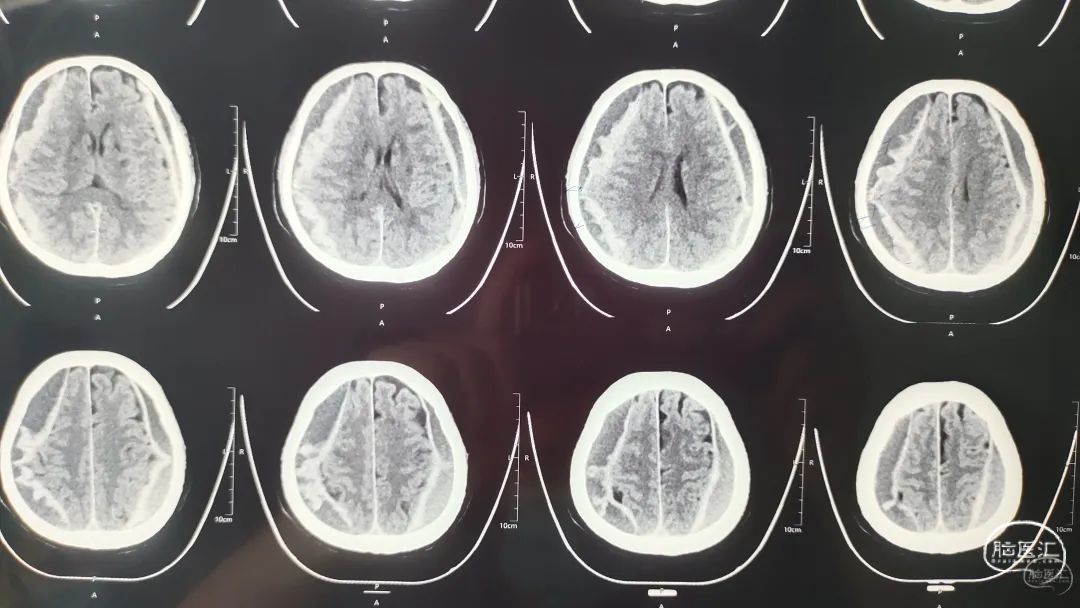

术前CT

患者双侧亚急性硬膜下血肿,血肿混杂密度,神经内镜下血肿清除术。

术后复查